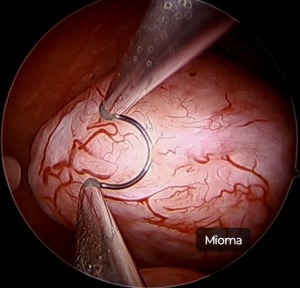

Miomectomia Histeroscópica

Consiste na retirada de miomas por vídeo com a utilização de histeroscópio. Indicado para casos de miomas submucosos que causam sintomas.